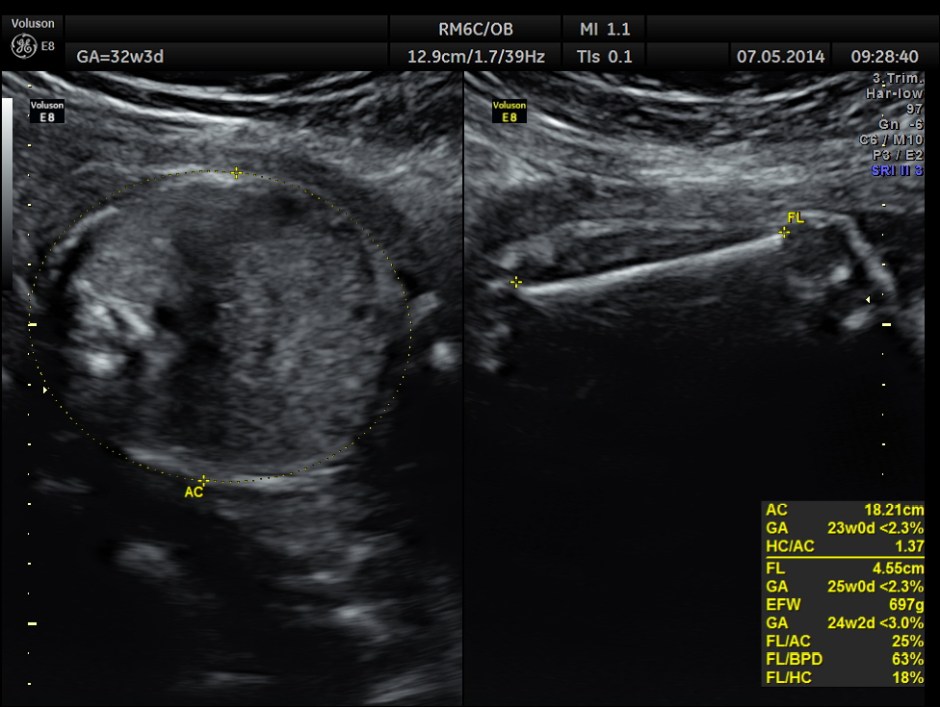

This was a 37 year old lady , a primi gravida referred for evaluation of intra uterine growth restriction. As per LMP the GA was 32 w 3 Days, but as per AUA the GA was 26 weeks . All the long bones were < 5.0 % tile. But cerebellum was 42.7 % tile. There was severe symmetrical growth restriction .

The echo pictures are given below.